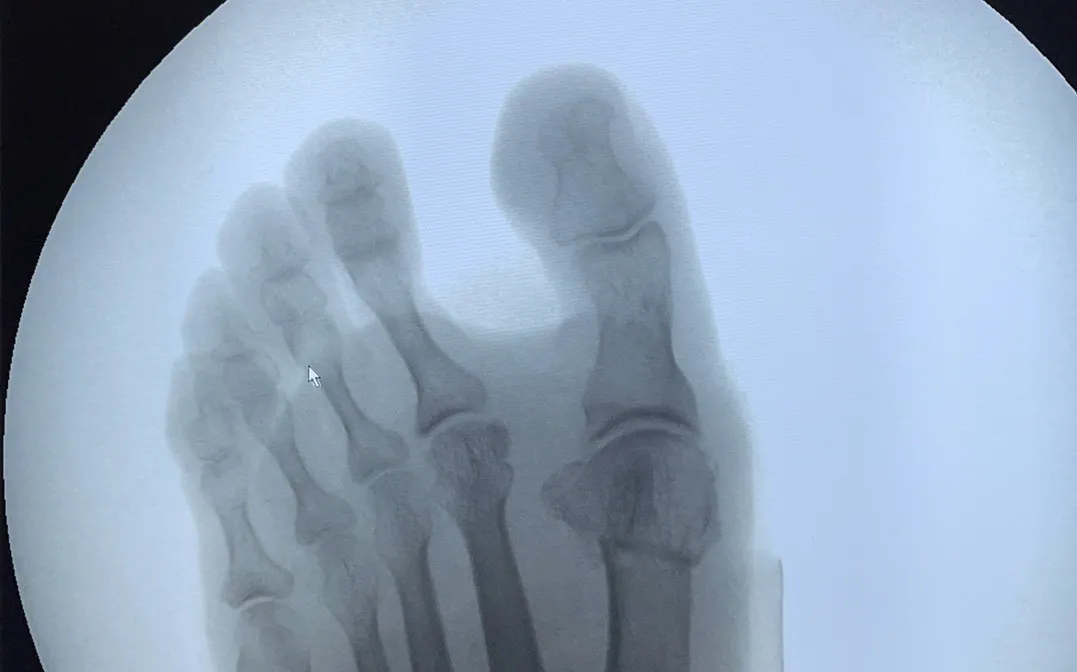

微創(chuàng)矯形助您重拾自信

對(duì)于拇指外翻的干預(yù),通常分為非手術(shù)和手術(shù)兩種方式。對(duì)于非手術(shù)干預(yù)無效或癥狀嚴(yán)重影響生活的患者,微創(chuàng)矯形手術(shù)是一個(gè)理想的選擇。

>>>微創(chuàng)矯形手術(shù)的優(yōu)勢(shì)

?創(chuàng)口大小:術(shù)后創(chuàng)口僅0.5-1cm,疤痕不明顯;

?治療時(shí)長(zhǎng):雙腳手術(shù)僅需30-40分鐘;

?術(shù)后恢復(fù):術(shù)后即可穿戴矯正器,6小時(shí)后可下地行走,6周后可正常穿鞋生活;

?日常生活:微創(chuàng)手術(shù)能有效矯正拇趾外翻,緩解疼痛,改善足部功能。